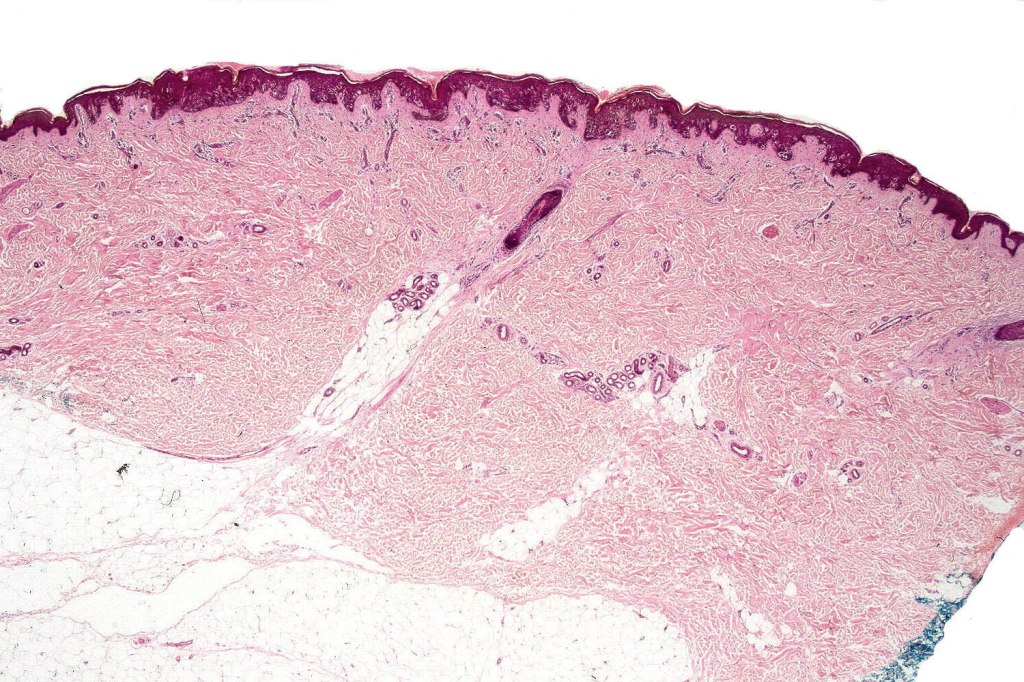

This is a rare, intraepidermal variant of Spitz nevus. It presents more commonly on the extremities of females as a <6.0 mm, pigmented maculopapule. Age distibution ranges from 15-57 years (mean 34)

Histological features

•Variable acanthosis

•Superficial dermal inflammatory cell infiltrate